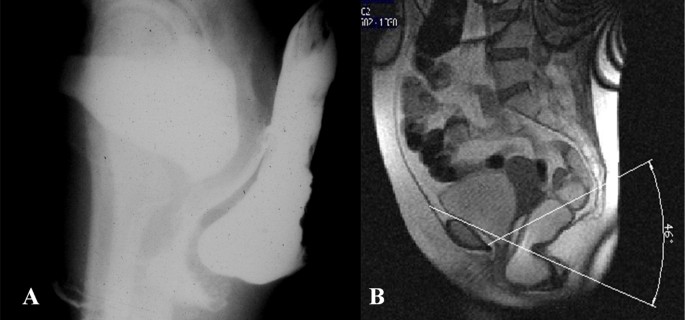

Rectocele could be defined as an out-pouching of the anterior rectal wall occurring during evacuation or straining [15–17] (Figure 1a-b).

Pelvic floor hernias could be classified, basing on the content, into enterocele, omentocele, and sigmoidocele, whereas, according to the hernia development they could be classified as elytrocele, edrocele, retrorectal, and Douglas' and Retzius' hernias [6] (Figure 2a-b).